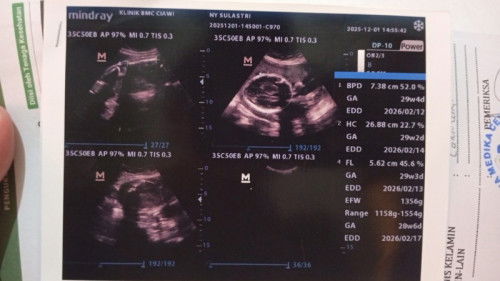

Posisi baby oblique, plasenta nutupin ½ jalan lahir.

Halo mom, aku mau tanya, apakah posisi plasenta yang menutupi ½ jalan lahir bisa berubah ? Jadi tadi usg, harusnya kalau menurut usg dari trimester 1, usia kandungan tuh 31 week 6 day, tapi tadi malah jadi 33 week 6 day. Terus posisi baby yang tadinya sungsang sudah bisa kebawah tapi masih belum lurus, ternyata posisi plasenta masih nutupin ½, yang bkin baby nggak bisa geser ke tengah. Sekarang jadi kepikiran banget, dan tiba2 sejak sore tadi tulang selangkangan rasanya nyeri gitu. Posisi plasenta masih bisa berubah nggak ya mom ? #mohonbantujawabbunda #firstmom #pregnacy #askmommies